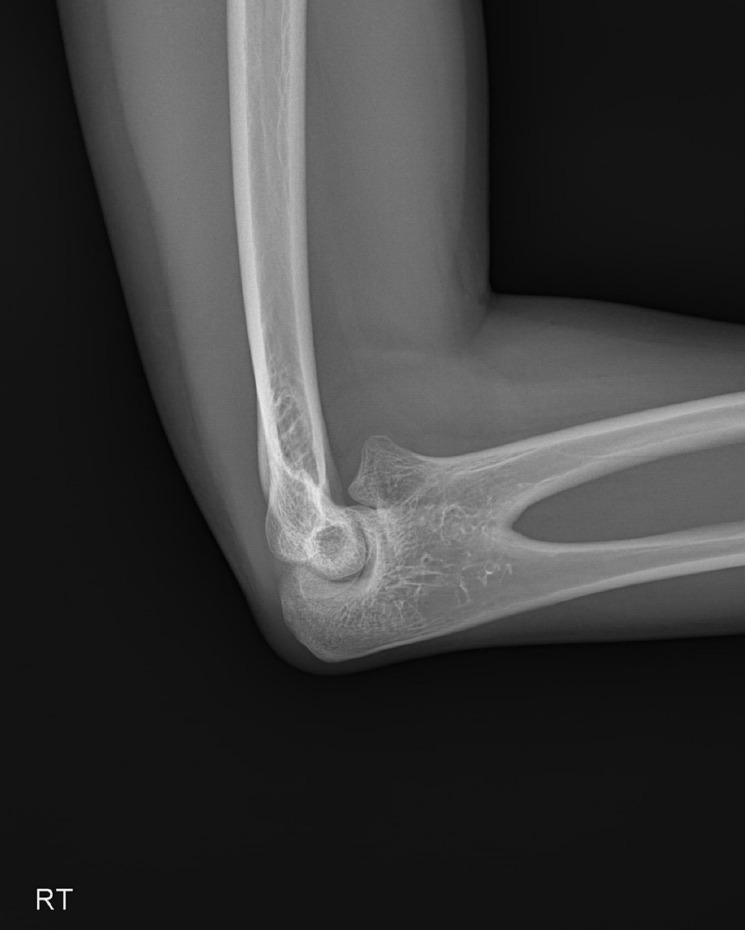

Spondylocarpotarsal synostosis syndrome (SCTS) is a rare genetic disorder characterized by vertebral fusion, short stature, and skeletal anomalies. SCTS is primarily associated with mutations in filamin B. However, in this report, we present a unique case of SCTS in a 28-year-old male who complained of neck and shoulder pain persisting for 1 year. His clinical presentation included radioulnar synostosis, cervical spine anomalies (scoliosis and agenesis of the posterior arch of C1), and a history of polydactyly. Genetic analysis revealed mutations in GMNN and DLL1. To the best of our knowledge, this is the first report on the association of SCTS with these genes.